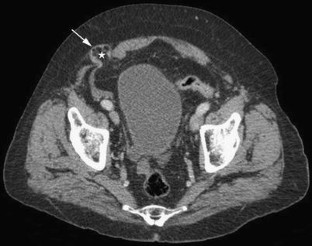

Fig. 1